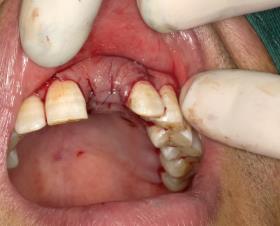

检查: 1. 口腔检查 全口咬合关系基本正常。21缺失,缺失区牙槽骨丰满度欠佳,牙龈状况一般,为厚龈生物型,全口牙龈普通退缩约1-2mm,临床牙冠偏长,牙龈乳头缺损;缺牙区邻牙未见明显倾斜,缺牙颊舌向宽度约5mm。患者为轻度氟斑牙,牙冠颈部为B4色,体部基底色为A3色,颈1/3与牙冠体部分界明显。其主要特征为牙面可见少量白垩色条纹。牙石及色素(++),牙齿轻度磨耗;开口型正常,开口度约三横指,笑线低。 2. 术前影像学检查 CBCT显示:21牙缺失。骨质III类。近、远中牙槽间隔顶至邻接点距离为6mm。牙槽嵴距离鼻底为20.43mm。缺失牙牙槽嵴宽度约4mm。

诊断:1、21牙缺失;2、慢性牙周炎 治疗计划 1、 诊治牙周黏膜疾病,行全口牙洁治。 2、 21牙行种植修复(考虑GBR技术) 处置: 21牙种植体植入术+GBR 患者入手术室,取仰卧位,术区行利多卡因+布比卡因阻滞麻醉,碧兰麻于21牙区行浸润麻醉。常规消毒铺单,待麻药显效后,于21牙槽嵴顶做近远中切口,剥离术区黏骨膜,11远中以及22远中做唇侧附加切口。显露术野,见22牙槽窝尚未完全骨充填,唇侧骨量不足。以刮匙刮除局部肉芽组织后,生理盐水冲洗冷却下1.4mm直径球钻确定种植位点,先锋钻确定种植体植入方向。3.5-4.3mm扩孔钻逐级扩大种植窝洞,收集钻头内残留的自体骨备用。用4.3mm攻丝钻在骨壁上攻丝,再用扭矩扳手将种植体旋入。旋上覆盖螺丝,种植体唇侧颈部可见骨缺损区,在骨缺损区周围用小球钻制备多个营养孔。并在唇侧黏膜瓣底部做减张切口,切断黏骨膜,制备复合瓣。收集术区血液,将自体血与骨替代材料混合覆盖于骨缺损区。修剪生物屏障膜至合适的大小和形状,将屏障膜覆盖于骨替代材料上,用自体血液湿润屏障膜至良好贴附状态。无张力关闭牙槽嵴顶切口以及附加切口。常规止血,术毕。 6个月后行种植修复,安置修复基台,戴入修复体后可见龈乳头未安全再生。